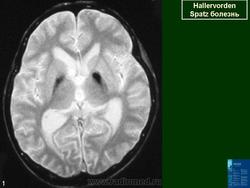

ГМ. Галлервордена - Шпатца болезнь. +

Галлервордена - Шпатца болезнь

Болезнь Галлервордена - Шпатца - наследственное заболевание экстрапирамидной системы, связанная с нарушением обмена железа и липидов и повреждением бледного шара и черной субстанции. Тип наследования аутосомно-рецессивный. При патоморфологическом исследовании характерным признаком является гиперпигментация бледного шара и черной субстанции. Обнаруживается пигментация коры полушарий большого мозга и таламуса. Пигмент находится внутри невронов и глиальных клеток, расположенных около сосудов; содержит железо (вместе с тем каких-либо нарушений обмена железа в организме не обнаружено). Наблюдаются утолщение и фрагментация аксонцилиндров в пораженных областях. Постепенно наступает дегенерация невронов коры полушарий большого мозга и мозжечка. Характеризуются нарастающей экстрапирамидной ригидностью, гиперкинезами (атетоз, торсионная дистония), затем развивается акинетико-ригидный синдром, пирамидная микросимптоматика, снижение интеллекта. Течение медленно прогрессирующее на протяжении 10 - 20 лет.

"Глаз тигра"-наглядно и красиво.